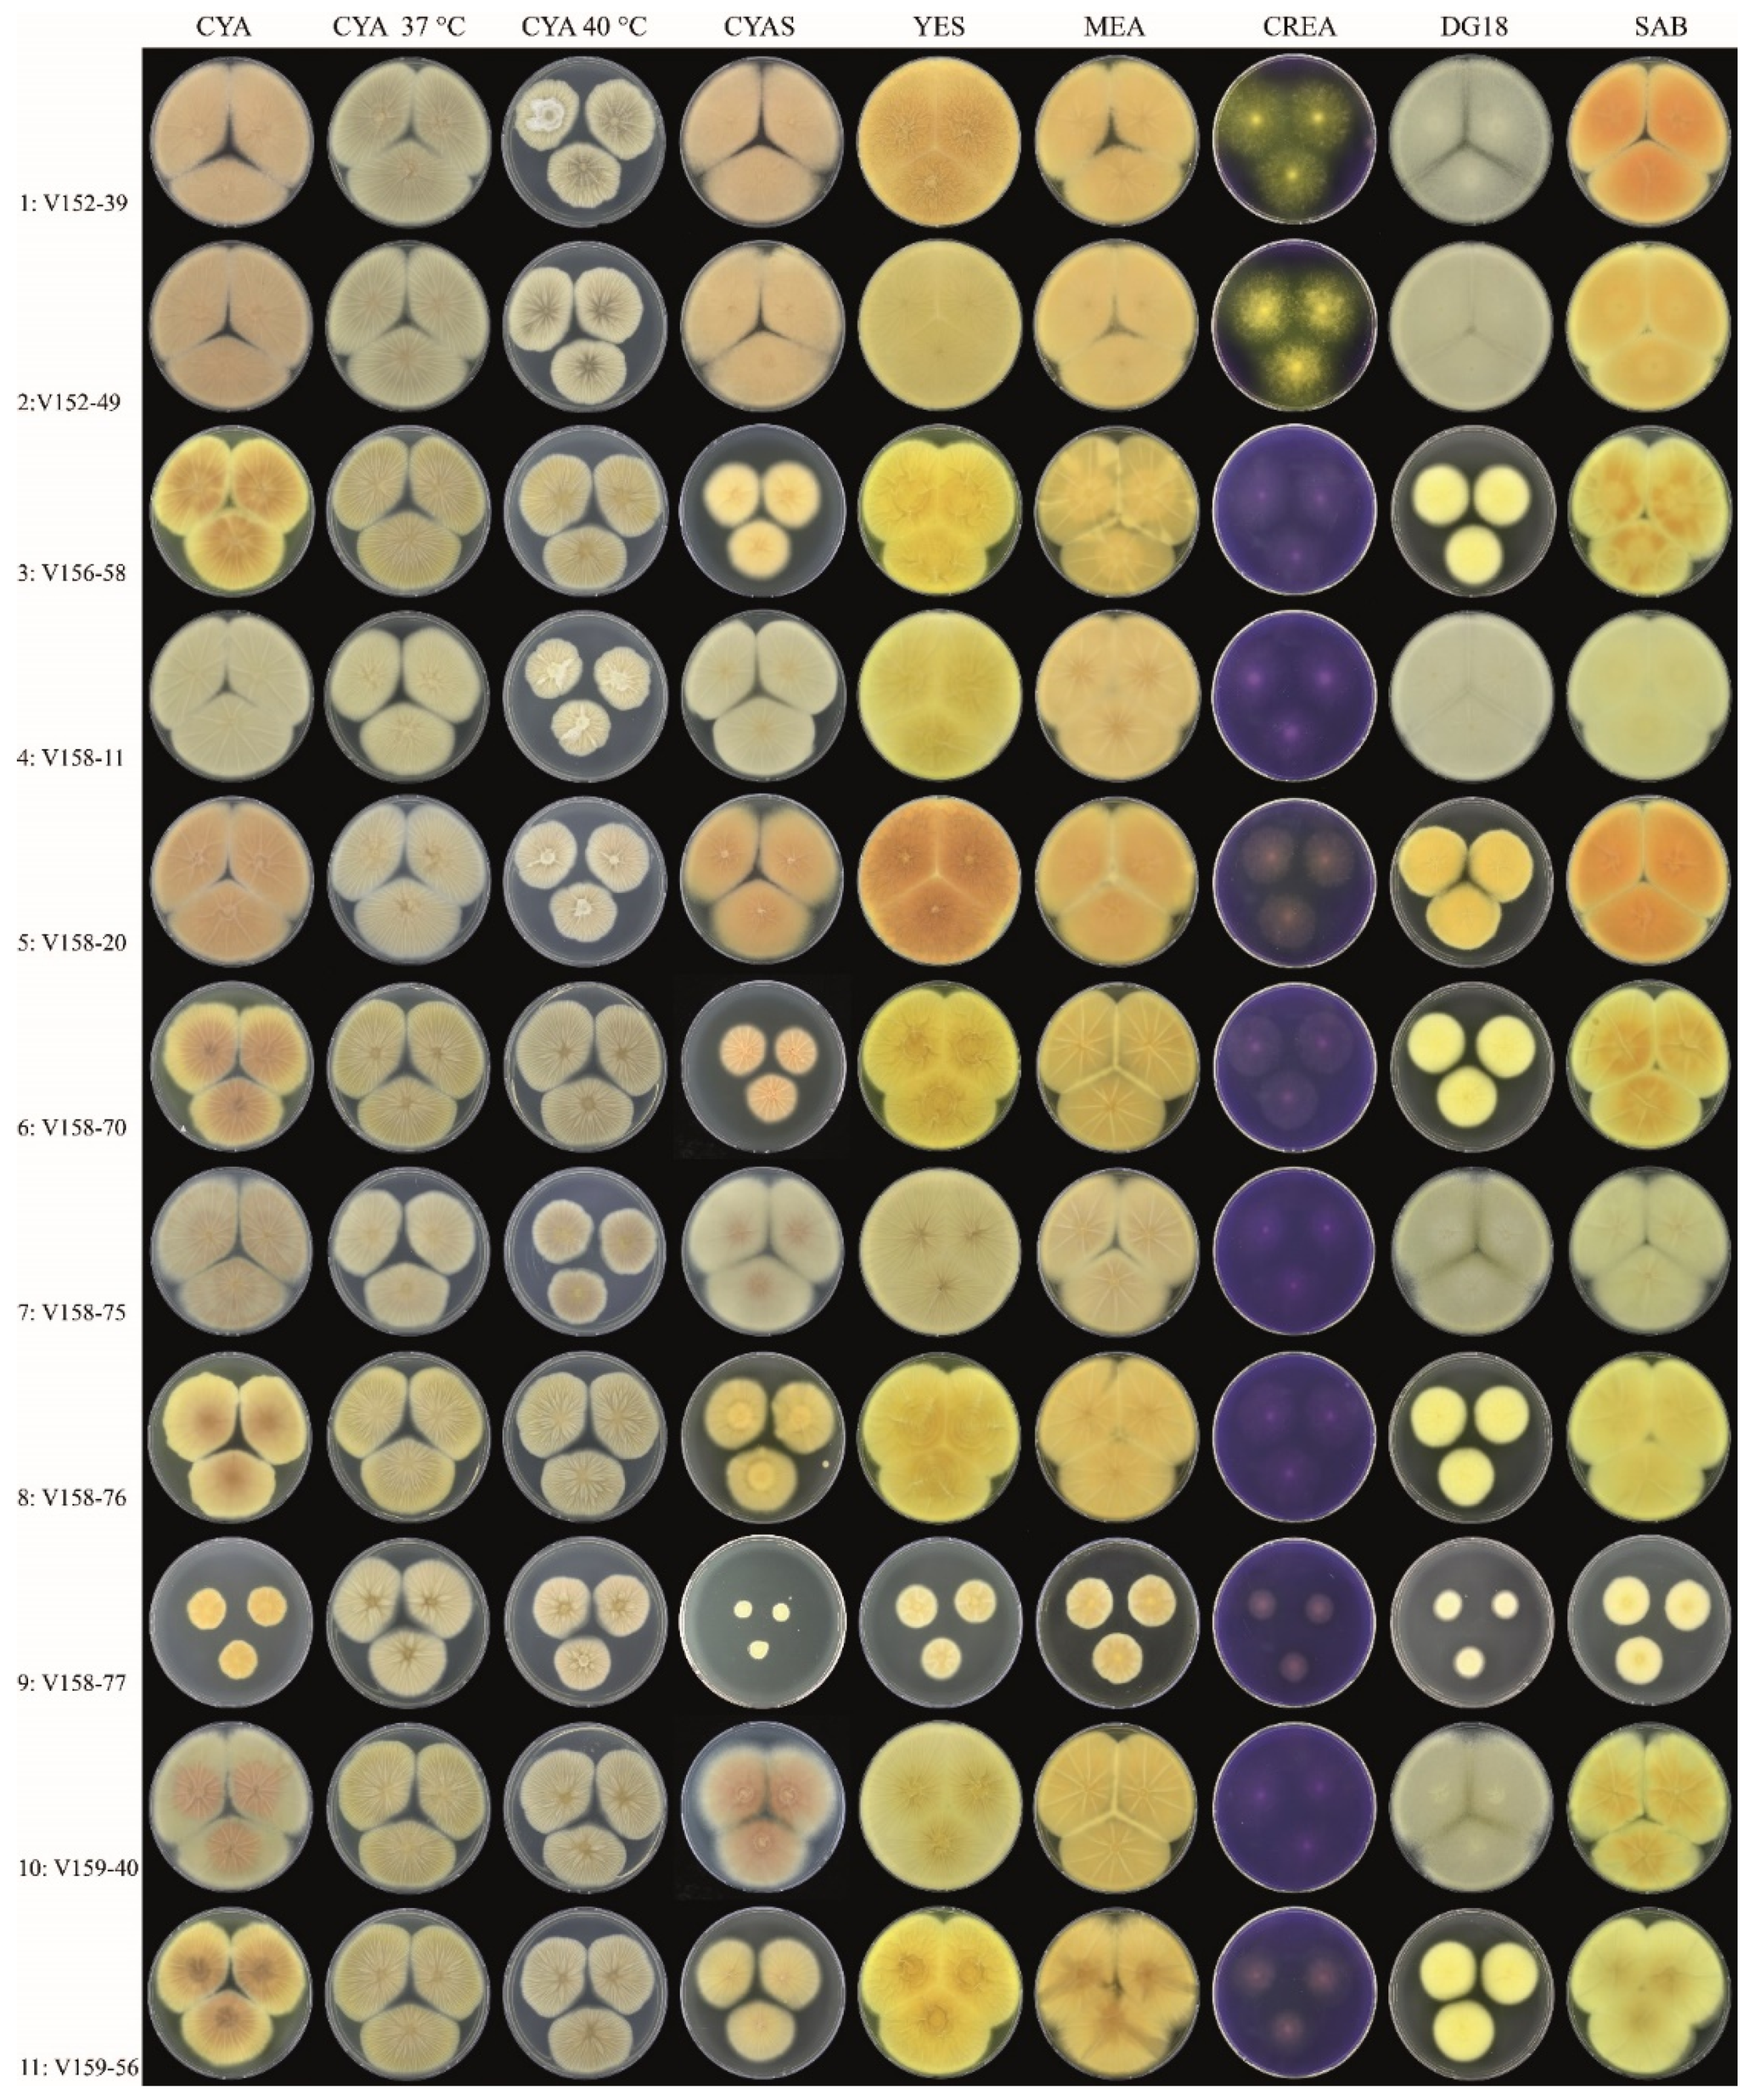

3.1. Strains, Phenotypical Analysis and Genotyping

| Isolate | Amino Acid Change | Colony Diameter (mm, after 7 d, 25 °C) | Unique Macromorphological Characters Compared to Isolates 1–2 a | ||||||||||||||

|---|---|---|---|---|---|---|---|---|---|---|---|---|---|---|---|---|---|

| I997N | R52G | A221T | V99A | H25Q | P38L | A561T | Y119F | K1757R | I570T | T159I | R669Q | E35* | P445L | CYAS | DG18 | ||

| 3 | x | x | x | x | x | x | x | x | x | x | 36–38 | 32–34 | Colony diameters smaller on DG18 and CYAS, sporulation variable | ||||

| 4 | x | x | x | x | 50–53 | >60 | Colony diameters slightly smaller on CYAS; greenish-brown-colored conidia | ||||||||||

| 5 | x | x | x | x | x | x | x | x | 54–58 | 36–38 | Colony diameters smaller on DG18, slightly smaller on CYAS; sporulation generally absent or weak | ||||||

| 6 | x | x | x | x | x | x | x | x | x | 26–30 | 32–34 | Colony diameters smaller on DG18 and CYAS; sporulation variable | |||||

| 7 | x | >60 | >60 | Colony diameters similar as Isolates 1–2; abundant sporulation on all agar media, except creatine agar | |||||||||||||

| 8 | x | x | x | x | x | x | x | x | x | 36–38 | 29–32 | Colony diameters smaller on DG18 and CYAS; sporulation variable | |||||

| 9 | x | x | x | x | x | x | 8–10 | 16–18 | Colony diameters restricted on all agar media; sporulation absent | ||||||||

| 10 | x | 54–58 | >60 | Growth diameters slightly smaller on CYAS, sporulation generally moderate or good | |||||||||||||

| 11 | x | x | x | x | x | x | x | x | 35–38 | 30–33 | Colony diameters smaller on DG18 and CYAS; sporulation variable | ||||||